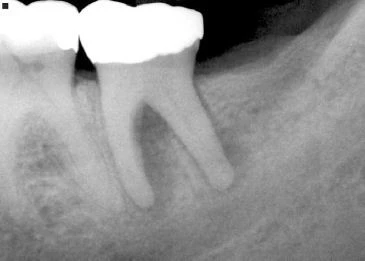

Bác sĩ cần chú ý đến những thay đổi bất thường trên X quang như mất xương rộng nhưng chỉ khu trú ở một răng và không có bệnh lý nha chu tiến triển. Điều này có thể gợi ý nứt dọc chân răng hoặc chia chân răng. Khi nghi ngờ có nứt dọc chân răng, bác sĩ cần chú ý tìm những dấu hiệu sau:

- Ống tuỷ rộng hơn bình thường so với ống tuỷ của chân răng cạnh đó

- Vùng thấu quang xuất hiện giữa trục chính của vật liệu trám bít ống tuỷ (hoặc chốt) và thành ống tuỷ.

- Vùng mất xương ở phía gần và xa chân răng. Khi nứt dọc chân răng hoặc chia chân răng mở rộng từ phía gần đến phía xa của răng thì thường toàn bộ dây chằng nha chu quanh răng sẽ giãn rộng không điển hình

Hình 14. Tiêu xương rộng khu trú quanh một răng, những răng cạnh đó bình thường, gợi ý một trường hợp nứt dọc chân răng

Hình 15. Khi răng có ống tuỷ rộng hơn so với răng cùng loại hoặc so với răng cạnh nó thì nên nghi ngờ có nứt dọc chân răng

Hình 16. Khi có khoảng trống giữa chất trám bít ống tuỷ và thành ống tuỷ thì nghi ngờ cao có chia chân răng.